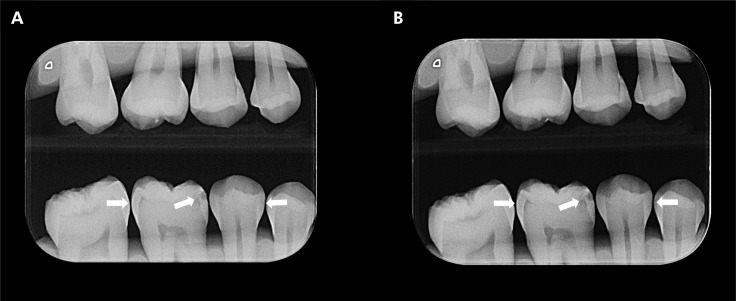

This study aimed to evaluate the influence of a portable X-ray device on the diagnosis of proximal caries lesions. For that, radiographs of 40 human teeth with white spots or color changes in enamel and/or dentin were acquired using the Eagle X-ray portable device (Alliage, São Paulo, Brazil) set at 2.5 mA, 60 kVp and an exposure time of 0.5 s (1.25 mAs). Then, new radiographs of the teeth were acquired using the Focus X-ray wall-mounted device (Instrumentarium, Tuusula, Finland) set at 7 mA, 70 kVp, and exposure time of 0.16 s (1.12 mAs). Five oral and maxillofacial radiologists individually assessed the radiographs. Area under the receiver operating characteristic curve (AUC), sensitivity, and specificity were calculated from the responses of the five examiners and compared between the devices tested using Student's t test. Significance level was set at 5% (α = 0.05). The weighted Kappa index evaluated the intra- and inter-examiner agreements for caries lesions diagnosis. The use of a portable X-ray device did not influence on AUC, sensitivity and specificity metrics for the diagnosis of caries lesions (p > 0.05). The intra- and inter-examiner agreements for the caries lesions diagnosis ranged from substantial to almost perfect (0.646-0.859) and moderate to substantial (0.491-0.617), respectively. The diagnostic accuracy for detecting proximal caries lesions is not impaired when using a portable X-ray device.